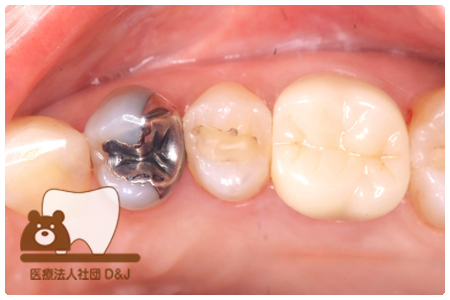

症例3フリジルコニアクラウン 左上6

治療前

治療後

59歳 男性

- 治療内容

- 虫歯で大きく失われた歯に対して、土台としてファイバーコアを使用し、その上にフルジルコニア製の被せ物を装着しました。見た目と強度を両立した自由診療の治療です。

- 治療期間

- 根の治療含めて3カ月半

- 費用

- 自費

フリジルコニアクラウン:77,000円(税込)

(R8.2月時点)

- その他の治療の費用は含まれておりません。

- リスク・副作用

- 強い力が加わると割れる可能性があります。また、噛み合わせや歯ぎしりの影響で脱離することがあります。